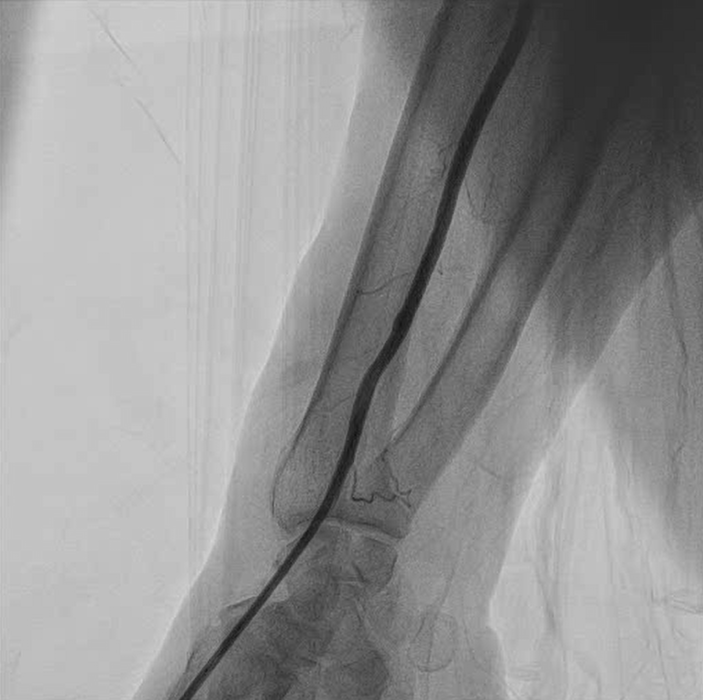

Because of the absence of injectable thrombin solution and the frail condition of the patient, it was decided to proceed with an endovascular approach. A 6F sheath was introduced in the distal radial artery (Figures 1 and 2, Video 1). Using a 6F Judkins catheter, a 0.014-inch guidewire was introduced inside the radial artery through the base of the RPA and distal to the brachial artery. A 3 x 24-mm polytetrafluoroethylene-covered stent was deployed initially, but with residual leak (Figure 3, Video 2). A second 3 x 18-mm covered stent was deployed, with minimal contrast flow inside the RPA. Final post-dilatation was performed with a 3.5 x 15-mm noncompliant balloon, with no residual flow inside the pseudoaneurysm. (Figure 4, Videos 3 and 4).